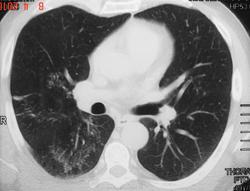

Работает машинистом в метрополитене. Мат.бытовые условия удовлетворительные. Считает себя здоровым. Ан. Крови, мочи – норма. МБТ(-) методом люминесцентной микроскопии в 3 - х пробах. Реакция на пробу Манту – 16 мм. В легкхих дыхание везикулярное. Хрипов нет. Имеются фрагменты рентгенологической документации (представлены) выполненные в амбулаторных условиях. Диагноз оставался неясным. Был направлен в другое учреждение для дообследования. Вчера узнал об окончательном диагнозе. Больной из - под наблюдения выбыл в другой район города. Хотелось бы услышать Ваше мнение о предварительном диагнозе по результатам представленных материалов. Дайкома точно нет. С уважением Nikolas

1)уплотнение по типу матового стекла,2)утолщение междольковых перегородок ,3)синдром очаговых теней (перилимфатически и центрилобулярно),4)утолщение стенок бронхов,5)единичные участки центрилобулярной эмфиземы,6)преимущественная локализация в в верхних долях (вероятнее всего лимфогенный путь распросранения),7)кистозная перестройка (отсутствие в них визуализации центрилобулярного комплекса).необоходимо исключить гранулематозы,в первую очередь 1)гистиоцитоз,2)туберкулез,3)саркаидоз.дальше 4)экзогенный аллегический альвеолит,5)вирусная пневмония .клинику в студию пожайлуста

Пациент был обследован в ПТД. При бронхоскопии - норма. Диагноз туберкулеза был поставлен под сомнение и больной госпитализирован в пульмонологическое отделение. Однако через 1 месяц три пробы мокроты дали рост МБТ (чувствительные ко всем противотуберкулезным препаратам). Больного перевели в противотуберкулезный стационар, где также были выявлены МБТ методом посева. После лечения наблюдалась выраженная положительная динамика туберкулезного процесса (со слов коллеги). Попытаюсь найти больного и представить все материалы. Ошибочное заключение можно объяснить недостаточным знанием отличительных признаков подострого диссеминированного туберкулеза легких и диссеминированных процессов другой этилогии. КТ диагностика туберкулеза легких требует дальнейшего изучения целым коллективом исследователей, а не переписыванием зарубежных работ. Желаю всем удачи. Присылайте материалы с диссеминированным туберкулезом легких. С уважением Nikolas

Cпециалисты по КТ диагностике упустили самое главное - реакцию Манту 16мм. При саркоидозе такой не бывает.

Толщина 3 мм слишком много! Надо было сделать реконструкции с меньшей толщиной среза. Тошда было бы видно "дерево-в-почках" хорошо; При саркоидозе оно практически никогда не встречается - там такие мелкие очажки сливаются в конгломераты но дерево-в-почках не дают. При наличии дерева-а-почках должен всегда первым делом подозреваться АКТИВНЫЙ воспалительный процесс. При поражении верхних долей (особенно 2-й сегмент) или 6 сегментов должен подозоеваться специфический процесс.

То есть : "дерево-в-почках"+"верхние доли" = исключать первым делом активный туберкулез. Если скопия мокроты не дает результато а надо решить срочно и ждать времени нету - то за рубежом часто делают ФБС с ПЦР промывных вод бронхов (селективно берут ихз наиболее пораженной зоын). Это позволяет исключить и опухоль. (ведь бронхиолит может давать и опухолевый процесс, и другие гранулематозы и тд).

Лимфоузлов кстати тоже увеличенных явно не видно. Конечно такое можно встретить при 3-й стадии саркоидоза, но если честно из всех саркоидохов что я видел ОЧЕНЬ небольшое их количество было без увеличенных лимфоузлов. В основном при такой картине как выше всегда имееются увеличенные корневые и правая паратрахеальная группа (в разной степени конечно). КРомсе того нету более характероного дял туберкулеза сбплеврального поражения (по ходу междолевой плевыр например и по ходу костальнйо плеверы)

Кончено мне легко писать ретроспективно зная диагноз. Но все таки решил написать. В плане диф/ диагноза саркоидоза КТ ОЧЕНЬ специфично и в данном случае картина конечно визуально похожа на саркоидоз, но только в связи с тем что предоставлены КТ-томограммы недостаточного качество, не позволяющие четко отдифференцировать перилимфатическое распредления очагов при саркоидозе (без дерева в почках) и типично бронхогенное распространение (с наличием "дерева-в-почках")

Пусть не вводит в заблуждение "матовое стекло". То что первично обычно принимается за матовое стекло на 3мм срезах - является эффектом усреднения за счет множественных мельчайших (1-2 мм) очажков.

Вообщим, при подозрении на саркоидоз или другой диссеменироаный процесс толщина среза в 3 мм - СЛИШКОМ БОЛЬШАЯ! Хотите более достоврено оценить характер распределения очагов - делайте по 0.5 или 1 мм). Большинство современных спиральных томографов так и снимает. А потом все реконструируется в 2.5 мм или выше для снижения шума и удобства хранения. Но все равно при наличии мелких очажков надо просматривать сканы с минимальной толщиной среза для установления взаимоотношенря очагов по отношению к вторичной дольке.